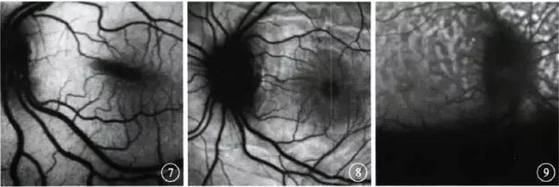

FAF检查发现,病程2~4个月的

6例12只眼未见明显视网膜色素

上皮(RPE)改变,但可见血管管

径增粗、走形纡曲(图7);其中

脉络膜皱褶2例4只眼可见强弱

不一的线条状荧光(图8)。病程

>2年的4例8只眼眼底呈豹斑

状荧光,与FFA强荧光区域对应处

FAF呈弱荧光;与FFA弱荧光区区域

对应处FAF呈强荧光(图9)。

图7病程2~4个月患眼FAF像。

未见明显RPE改变,可见血管管径

增粗、走形纡曲图8病程2~4

个月的脉络膜皱褶患眼FAF像。可

见强弱不一的线条状荧光 图9病

程>2年患眼FAF像。可见豹斑状

荧光,与FFA强高荧光区域对应处

呈弱荧光,与FFA弱荧光区区域对

应处呈强荧光